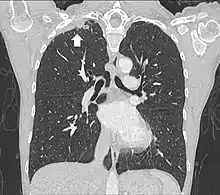

- Tumeur du compartiment antérieur

TDM d'une tumeur de Pancoast gauche envahissant l'arc antérieur de la 1re et de la 2e côte (flèche jaune).

PET-scanner du même patient[14].